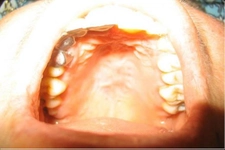

Doğumdan Sonra İyileşme Süreci

Doğumdan sonra kendiliğinden iyileşme süreci genellikle olumlu ve hızlıdır. Ancak bu süreçte yaşanan endişeler, özellikle ağrının yeniden ortaya çıkma ihtimali ya da iyileşme sürecinin uzaması gibi kaygılar, anneleri etkileyebilir. Dikkat edilmesi gereken noktalar arasında, yeterli sıvı alımı, dengeli beslenme ve ağız hijyenine özen göstermek yer alıyor.

Eğer bu süreç hakkında daha fazla bilgi sahibi olmak istersen, uzman bir doktordan destek alman faydalı olabilir. Bu sayede hem fiziksel hem de duygusal açıdan daha sağlıklı bir hamilelik dönemi geçirebilirsin.